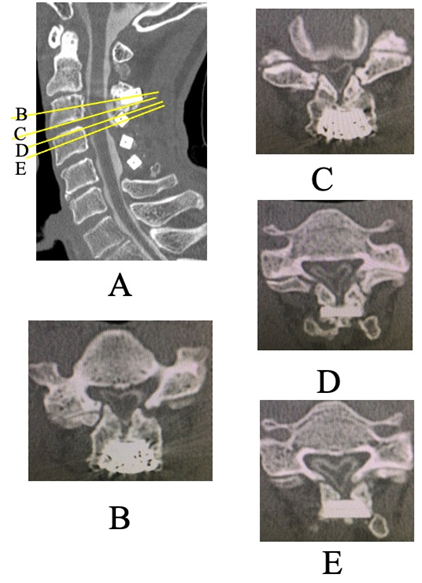

MRI showed spinal cord compression and signal changes at the C3 and C3/4 levels. CT myelography revealed non-union of the lateral gutters at C2 and C3 with osteophyte formation, and the lamina had reclosed. Marked spinal cord compression was observed at the C2–3 laminar level (Fig. 3).

Figure 3: Pre-operative computed tomography Myelography for the current surgery. (a) Sagittal view. (b, c, d, e) Axial view (b) C3 level (c) Inferior edge of C3 (d) Superior edge of C4 (e) C4 level. Pseudarthrosis and osteophyte formation at the lateral gutters of the C2 and C3 laminae, as well as laminar reclosure, were observed. Severe spinal cord compression was noted at the C2/3 laminar level.